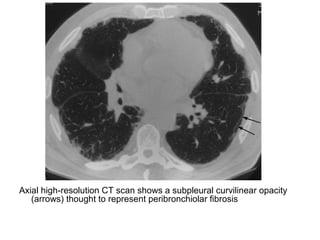

-HRCT :

*An early feature is a subpleural curvilinear opacity, this

finding represents peribronchiolar fibrosis

Axial high-resolution CT scan shows a subpleural curvilinear opacity

(arrows) thought to represent peribronchiolar fibrosis